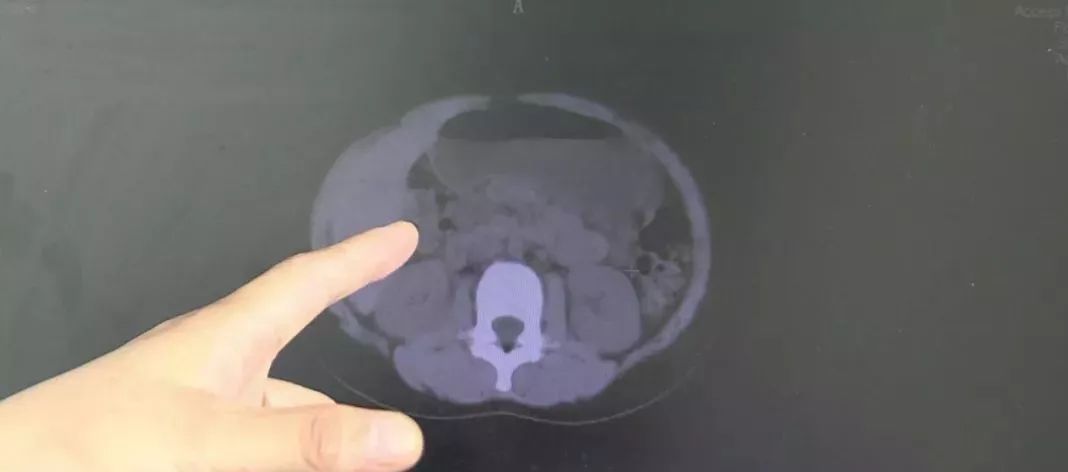

经过检查,医生发现,小岚的肠子里确实有很大问题。